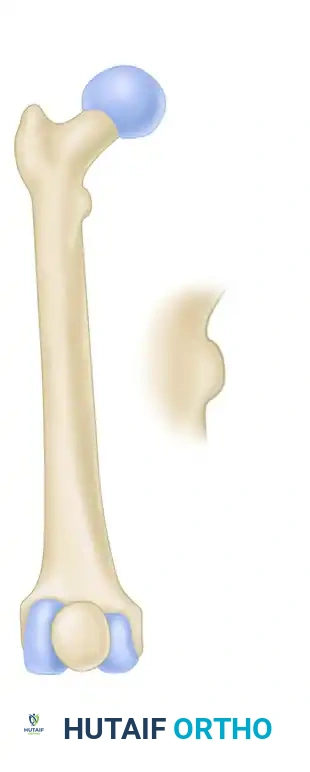

FIGURE 55-48: Proximal femoral locking plate fixation of a subtrochanteric femoral fracture with proximal extension. (A) Preoperative radiograph. (B) Preoperative axial CT scan shows extension proximally into the piriformis fossa. (C and D) Postoperative AP and lateral radiographs after fixation with a locking plate.